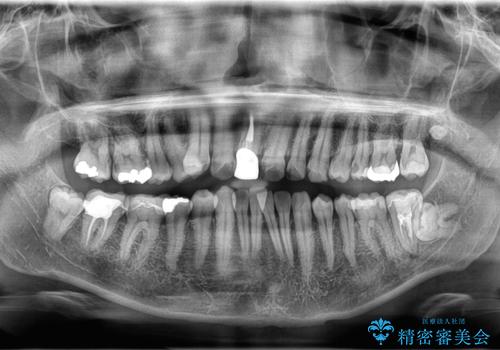

- 「八重歯と歯のでこぼこを治したい」を主訴に来院された患者様です。

歯は抜かずに奥歯の遠心移動とIPRで八重歯とでこぼこを改善しました。

左上3番は保険治療(CR)の劣化による二次カリエスになっていますので、後日治療予定です。